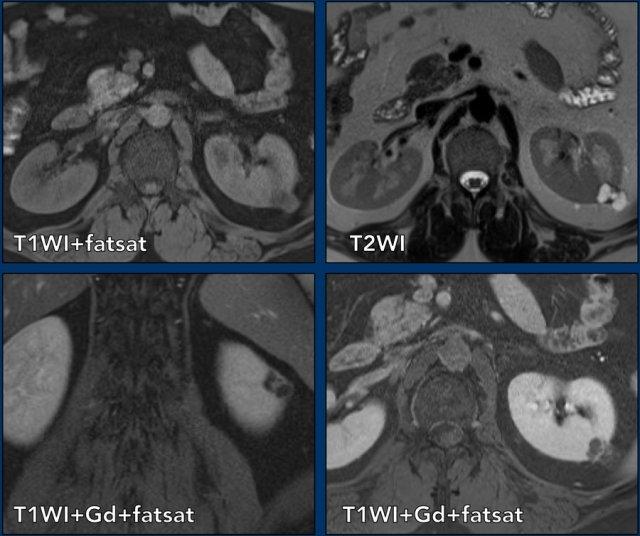

Ca lâm sàng 1

Cuộn qua các hình ảnh.

Ảnh T2W mặt phẳng axial và ảnh T1W mặt phẳng coronal có bão hòa mỡ và tiêm Gadolinium.

Có một khối dạng nang ở thận trái với nhiều vách ngăn mỏng ngấm thuốc.

Tổn thương được phân loại là Bosniak IIF.

Ca lâm sàng 2

Có một khối dạng nang ở thận phải với nhiều (> 4) vách ngăn mỏng, nhẵn, có ngấm thuốc.